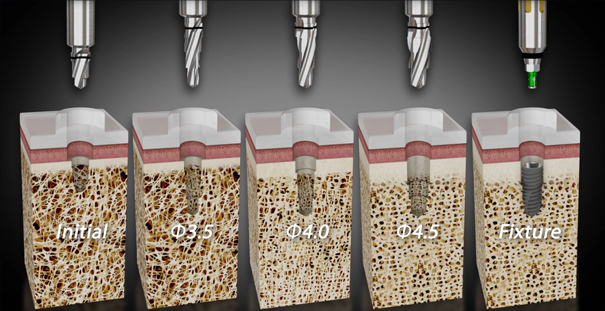

고난도 상악동 거상술 수술 과정

STEP 01

디지털 정밀 진단

STEP 02

상악동 점막 거상

STEP 03

골이식

STEP 04

골생성 확인

STEP 05

임플란트 식립